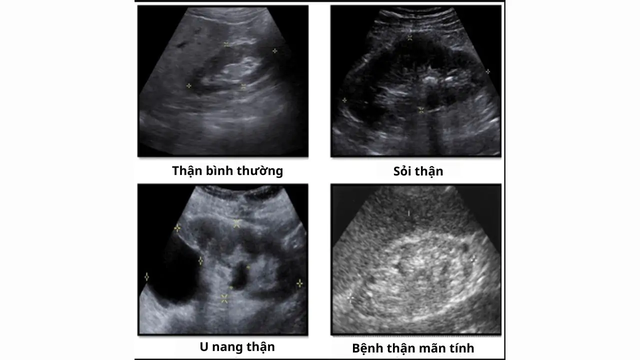

Siêu âm thận là kỹ thuật sử dụng sóng âm nhằm tạo ra hình ảnh về kích thước, cấu trúc hoặc các dấu hiệu bệnh lý của thận. Đây là kỹ thuật có giá trị cao trong chẩn đoán các bệnh lý khu trú ở thận như sỏi thận, nang thận, áp xe thận, thận ứ nước hoặc suy thận. Phương pháp này không xâm lấn, không gây đau, an toàn cho bệnh nhân và có độ chính xác cao.

Đặc điểm cho thấy siêu âm thận khỏe mạnh bình thường: Thận có hình hạt đậu, rốn thận nằm ở phía bên trong, kích thước 2 thận thường không giống nhau, có chiều dài khoảng 9 - 12cm, rộng khoảng 4 - 6cm và dày khoảng 3 - 4cm, đường bờ đều, nhu mô thận trái có hình tam giác (vì bên trái có lách đè vào). Khi siêu âm sẽ không quan sát được niệu quản ở người khỏe mạnh. Nếu thấy được niệu quản thì thường là do các bệnh lý dị dạng của niệu quản hoặc niệu quản bị giãn to. Siêu âm cũng thấy rõ động, tĩnh mạch thận.